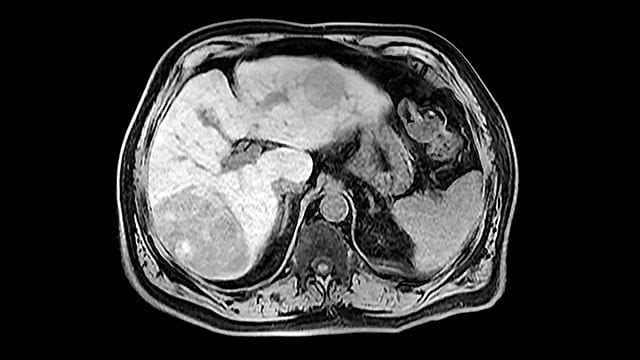

Despite major advances in immunotherapy, most patients with hepatocellular carcinoma (HCC) fail to respond to current immune checkpoint inhibitors. New research led by investigators now at Houston Methodist Hospital suggests an unexpected immune cell population — tumor-associated B cells — may be a key driver of resistance and a promising therapeutic target.

The study, led by Dr. Dan Duda, Ph.D., and published in the journal Nature Communications, shows that B cells infiltrating liver tumors can suppress the anti-tumor activity of T cells, limiting the effectiveness of immunotherapy.

The findings highlight a previously underappreciated component of the liver tumor microenvironment and suggest new combination strategies that could expand the reach of immunotherapy for patients with advanced liver cancer.